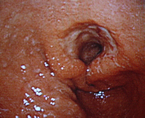

良性の胃ポリープと異なり、大腸ポリープはたとえ現在良性でも将来癌化する可能性があることが知られています。したがってある程度の大きさのポリープは切除することをお勧めします。当院では日帰りで可能ですが

「内視鏡下でポリープ切除が可能」とは言っても、これは手術に該当するものであり、大腸穿孔や術後出血などを引き起こす可能性があります。ポリープを切除した傷が完治するまでの2〜3週間は、食事制限、運動制限、禁酒など合併症予防のために遵守すべき事項があるので、手術を受ける際は厳守して下さい